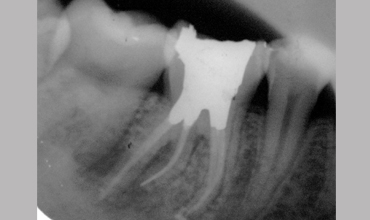

Management Of Radix Entomolaris In Mandibular First Molar